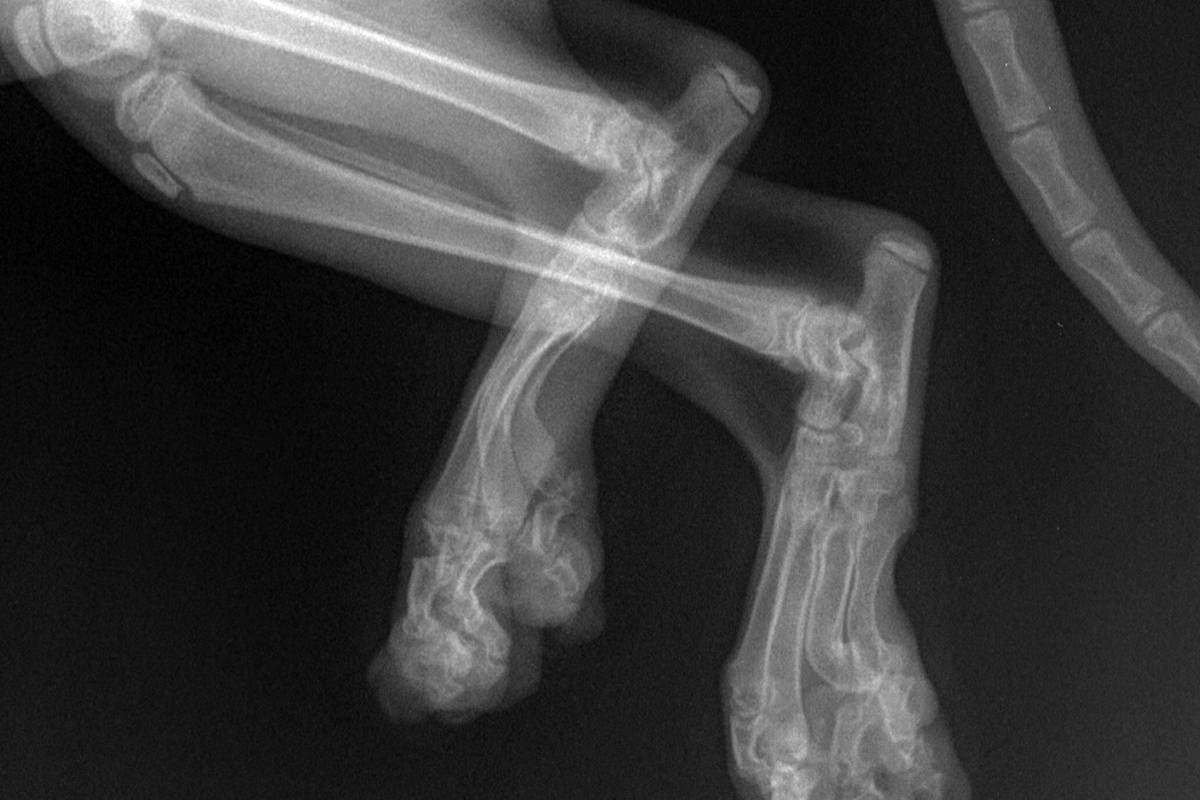

Остеохондродистрофия это наследственное заболевание, при котором развивается деформация не только ушей, но и скелета (укороченные искривлённые конечности, утолщенный хвост). Кошки, с проявлением остеохондродистрофии не могут прыгать, они не любят подвижных игр, походка у них «ходульная» или же прихрамывающая. Заболевание не сразу заметно. Кошки стараются перенести нагрузку на здоровую конечность, а так как вес кошек небольшой, то у них это получается довольно долго, до тех пор, пока не разовьётся артрит. Из-за недоразвития или деформации конечностей, кошки выглядят приземистыми или «присевшими». Хромота проявляется рано (с первых месяцев). Диагностируется данное заболевание с помощью рентгенографии.

Для постановки окончательного диагноза на остеохондродисплазию врач попросит предоставить родословную кошки. Возьмёт общий и биохимический анализ крови, анализ мочи. Сделает рентген конечностей и позвоночника. При рентгенологическом исследовании видны характерные изменения в области заплюсневого, запястного сустава и позвоночника.

Признаки болезни: укороченные, деформированные конечности, очень короткий, толстый хвост

Скорость прогрессирования, начало проявления клинических признаков и их выраженность может сильно отличаться у животных из разных пометов. Уши у шотландских котят начинают загибаться в возрасте около 1 месяца, а хромота и трудности при передвижении, связанные с остеохондродисплазией, проявляются обычно после отъема котят от матери, в возрасте 7 недель и старше.

Симптомы остеохондродисплазии:

- укороченные и деформированные лапки;

- неестественная, ходульная походка;

- хромота на одну или несколько конечностей;

- общие признаки болезненности (котенок мяукает при поглаживании, не играет, малоактивен, не может прыгать и бегать).

Косвенным признаком заболевания будет неестественно короткий, толстый, прямой и негнущийся хвост с тонким основанием. Из-за недоразвитых конечностей котенок имеет «присевший», приземистый вид.

Диагноз остеохондродисплазия ставят на основании поведенческих симптомов, внешнего осмотра, а также рентгенологического исследования, которое показывает нарушения в строении лап, позвоночника и хвоста.